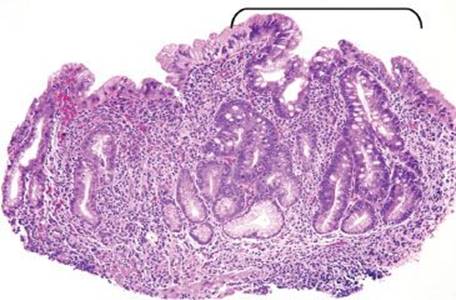

Figure 2.121 Lymphocytic gastritis pattern. The changes of lymphocytic gastritis are often prominent enough that they can be identified at scanning magnification, obviating the need for intraepithelial lymphocyte counts. The IELs usually affect the entire stomach but are more evident in the oxyntic mucosa and are more prominent in the superficial epithelium as compared to the deeper glands. Note the diffuse mixed inflammatory infiltrate in the lamina propria.

Lymphocytic gastritis differs from chronic gastritis by the presence of increased intraepithelial lymphocytes (IELs), defined as more than 25 intraepithelial lymphocytes per 100 epithelial cells (Figs. 2.120–2.126).38,91–97 The term “lymphocytic gastritis” was originally used to describe the histologic counterpart to “varioliform” gastritis (i.e., thickened rugal folds and erosions), but subsequent studies have shown this association in only 3.9% to 30% of cases. More commonly, the endoscopic image shows erythema but up to 50% of patients have a normal endoscopic appearance. Although the etiology of the inflammation remains unknown in up to 20% of cases, common associations include infection (e.g., Helicobacter, HIV), celiac disease and other immune-mediated disorders (common variable immunodeficiency, Crohn disease, lymphocytic enterocolitis), medications, and neoplasia (Figs. 2.127–2.142).98 As a result, recognition of the lymphocytic gastritis pattern can serve as an important red flag to the underlying diagnosis and, consequently, lead to effective therapy with resolution of symptoms. The changes affect the entire stomach, but intraepithelial lymphocytes are most evident in the oxyntic mucosa, and are more prominent in the superficial epithelium than the glands. Most cases show expansion of the lamina propria with a mixed lymphoplasmacytic inflammatory infiltrate, in addition to the intraepithelial lymphocytosis (Fig. 2.121). Regenerative and hyperplastic changes in the surface epithelium may be present, analogous to the surface changes seen with intraepithelial lymphocytosis of the small and large bowel. Immunolabeling identifies these as CD3+ T cells, with about 80% showing a cytotoxic/suppressor CD8+ phenotype. Most patients respond to treatment of their associated condition, when a known etiology is present (i.e., successful eradication of Helicobacter usually leads to reduced symptoms and decreased inflammation in biopsies, and adherence to a gluten-free diet typically results in clinical and histologic improvement in patients with celiac disease). Others advocate empiric Helicobacter eradiation, even in Helicobacter-negative patients. In general, immunosuppressive medications are reserved for those who fail gluten withdrawal and whose intraepithelial lymphocytosis involves the stomach, small, and large bowel. Untreated lymphocytic gastritis may persist for years, although spontaneous remission has been reported.